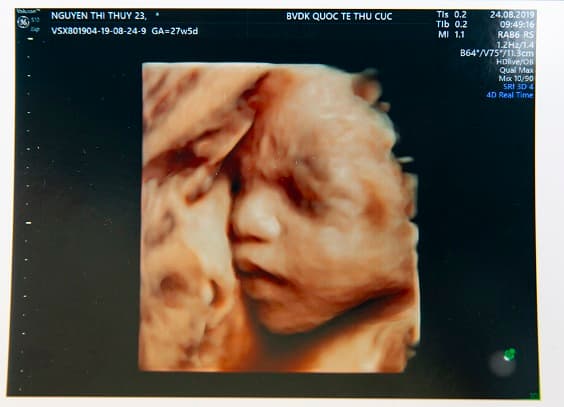

Siêu âm 5D là công nghệ siêu âm có khả năng tái tạo lại hình ảnh động của thai nhi trong bụng mẹ một cách rõ nét nhất. Cha mẹ sẽ có thể quan sát được cụ thể, rõ ràng từng chi tiết cơ thể của thai nhi như mắt, mũi, miệng, tay, chân, dây rốn, bánh nhau của bé, thậm chí thấy được một cách rõ ràng từng hành động nhỏ như khi bé nhếch mép, nhăn mũi, bĩu môi, cử động ngón tay… tất cả những hình ảnh này sẽ được thể hiện một cách rõ nét và sinh động như khi mẹ đang xem video trực tiếp vậy.

Siêu âm 5D có khả năng tái tạo lại hình ảnh động của thai nhi trong bụng mẹ một cách rõ nét nhất